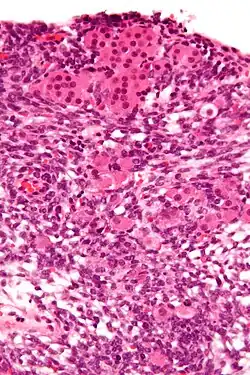

Micrograph of a Sertoli–Leydig cell tumour. The Leydig cells have abundant eosinophilic or light pink cytoplasm. The Sertoli cells have a pale/clear cytoplasm. H&E stain.

The tumour is subdivided into many different subtypes. The most typical is composed of tubules lined by Sertoli cells and interstitial clusters of Leydig cells.